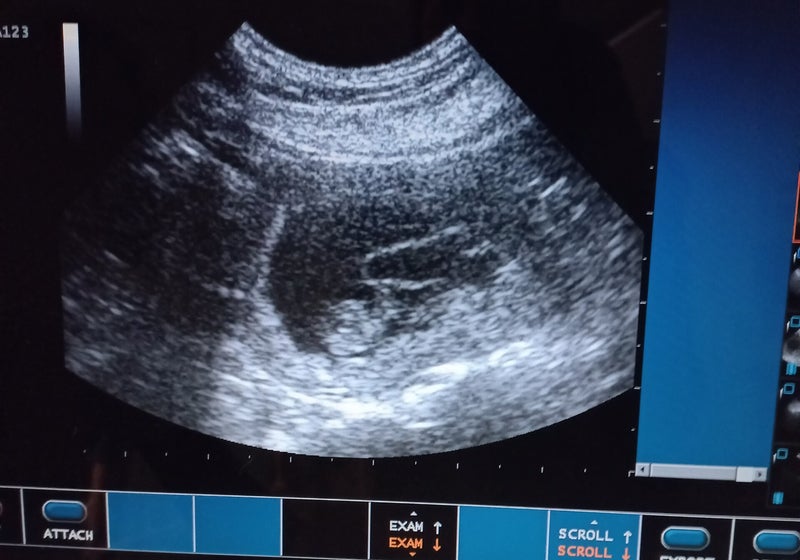

- 28 maart is de dracht bevestigd via een echo.

Sinds zondagmiddag lijken beide pupjes aan de betere hand, ze zijn weer rustig, slapen , ze drinken en groeien goed, ook tijdens de zware dagen bleven ze dit gelukkig doen. Eentje had maandag morgen een hoge temp waardoor ze nog 5 dagen extra anti biotica krijgen voor de zekerheid. We durven nog niet te hard te juichen en de angst zit er nog goed in.Het kan nu niet vast gesteld worden als het inderdaad om herpes gaat, als ons nog een pupje ontvalt zullen we hierop een sectie laten doen.De vermoedens zijn wel groot, ook omdat de echo uit wees dat Lola een groot nest zal krijgen, en bij de röntgen ineens een klein nest zichtbaar was, het zorgt voor embryo sterfte en er is ook een pup doodgeboren, wat symptomen zijn van het virus.